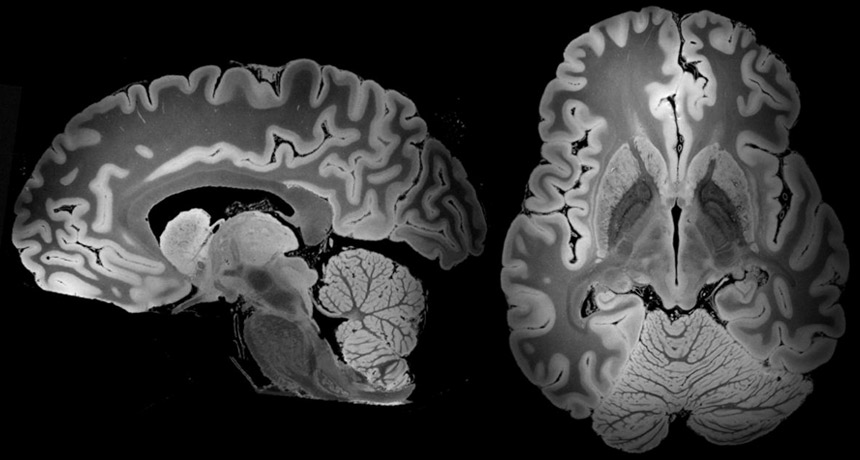

CLOSE-UP A 3-D view of the entire human brain, taken with a powerful 7 Tesla MRI and shown here from two angles, could reveal new details on structures in the mysterious organ.

B.L. Edlow et al/bioRxiv.org 2019